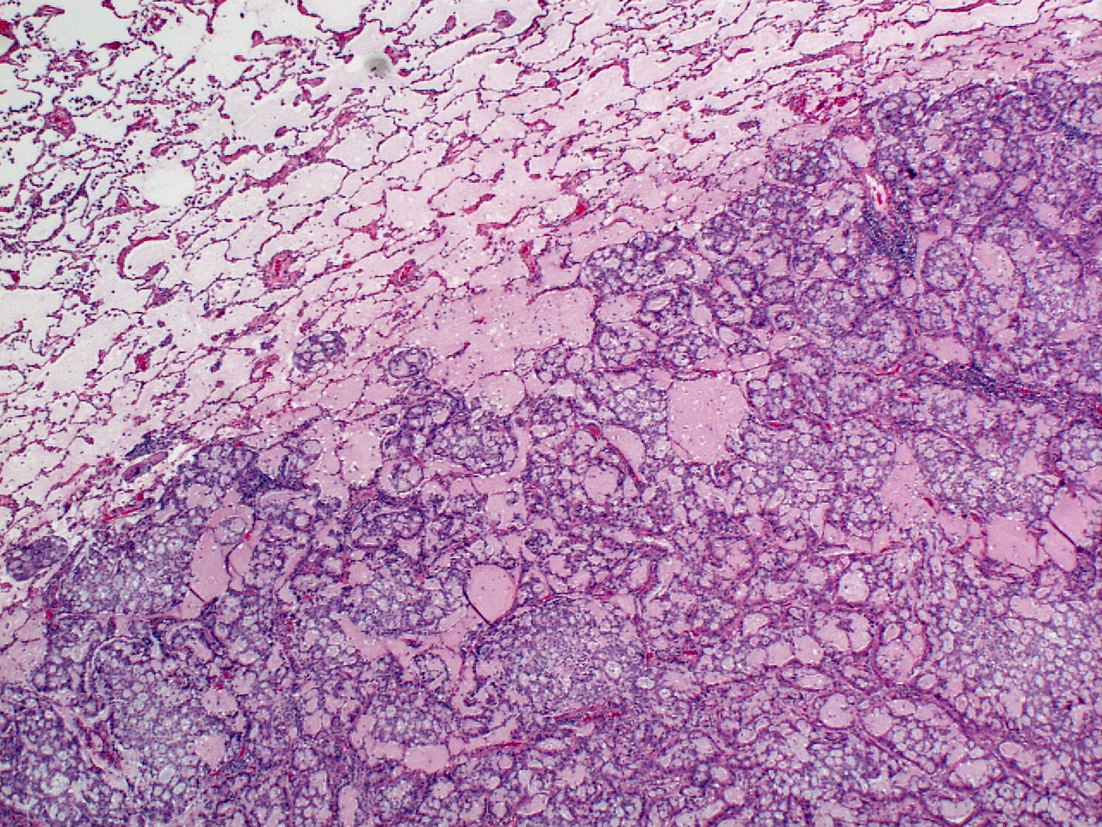

ASCCL报告ALK基因重排列流行性(反转EML4比其他移位常用性高)高可变性并直接依赖测试群使用高流行率偏差相关临床标准选择案例同EGFR突变一样,ALK重排列不是由烟草致癌驱动的,因此从不吸烟者中比较常见,但没有理由个人冒烟者不产生这种肿瘤。ALK重排列肿瘤患者趋势小于平均肺癌患者(中度-50s),但在EFGR变异中发现的性别差异一般在ALK正例中找不到基于语法选择案例对结果也有戏剧性效果和EGFR突变一样,ALK聚变是外围肺膜非单片驱动致癌物生物特征,即终端呼吸元件,并因此是如果所有NSCLC都测试ALK聚合值,则常用结果会低得多,视测试群中微量细胞癌的比例而定。稀有ALK重排列细胞癌报告,但这些案例异常,如果遇到,第一件事应该是质疑组织学诊断加上所有这些警告,报告流行率介于约2-7%NSCCL

使用双色分解探针的FISH测试仍被视为`gold标准'测试,主要是因为在早期临床测试中使用并验证了这一传统方法CrizotinibALK重排列NSCLCFISH测试后被美国药管局批准为Crizitib理疗辅助诊断,FISH测试要求至少50个可评估细胞至少读取50%,其中至少50%应显示非fedALK基因,通过三维和五维探针分离双直径或五维信号或丢失5信号来突出显示发现异常细胞小于这个百分比时,两位阅读者应评估100个细胞,异常细胞平均评分应超过15%-偏差图说明切除人工制品和各种不表示ALK基因重排列的其他偶发事件FISH相对昂贵耗时,需要特殊专业知识和设备,ALKFISH特别难读多肺癌样本中肿瘤细胞稀疏也使得阅读FISH难染色体原地混合式测试现可用ALK测试使用光场显微镜的长处是好保存形态学,但经验有限